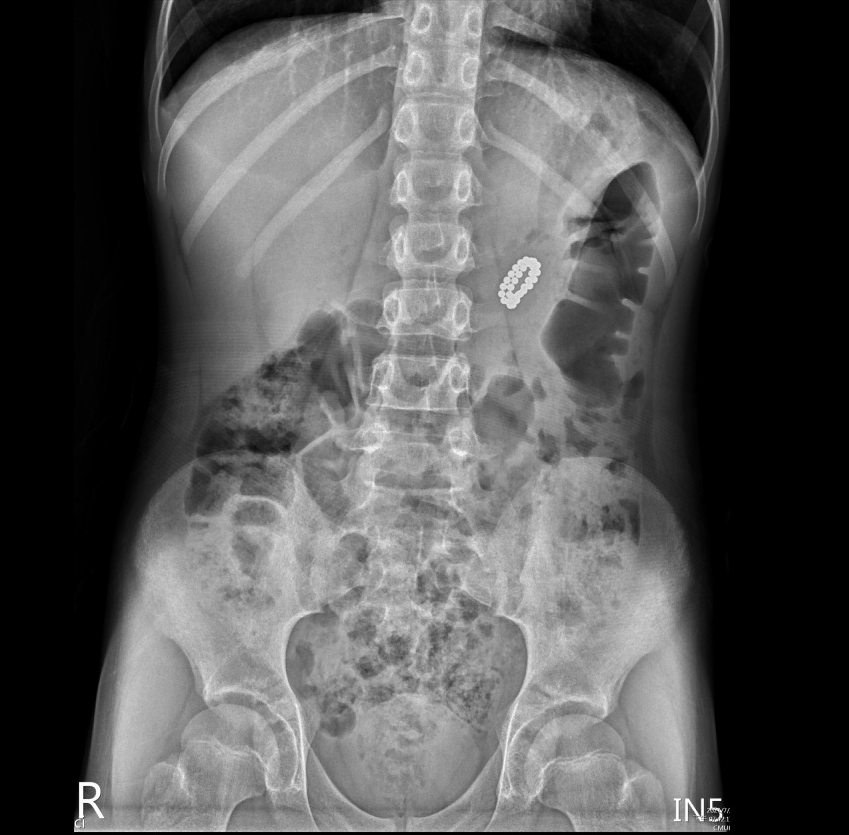

▲男童誤吞32顆磁力球,中國附醫兒童醫院團隊採「上消化道內視鏡」順利取出。(圖/中國附醫提供)

兒童肝膽腸胃科陳安琪主任表示,誤食磁力珠男童送院急診後,經腹部X光顯示,胃裡有約20~30顆磁珠,為了避免磁珠進入腸道之後造成重大併發症及開刀風險,與家屬充分說明後,由他與胡書瑋醫師安排無痛全身麻醉的「上消化道內視鏡」,順利取出串成像戒指大小的32顆磁力球,男童在術後良好,隨即出院返家。